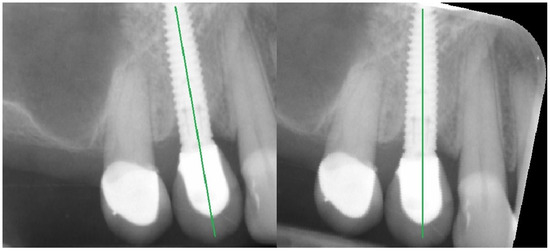

Figure 1.

Geometrical alignment of radiograph image. The green line marked on the implants indicates the long axis of the implant.